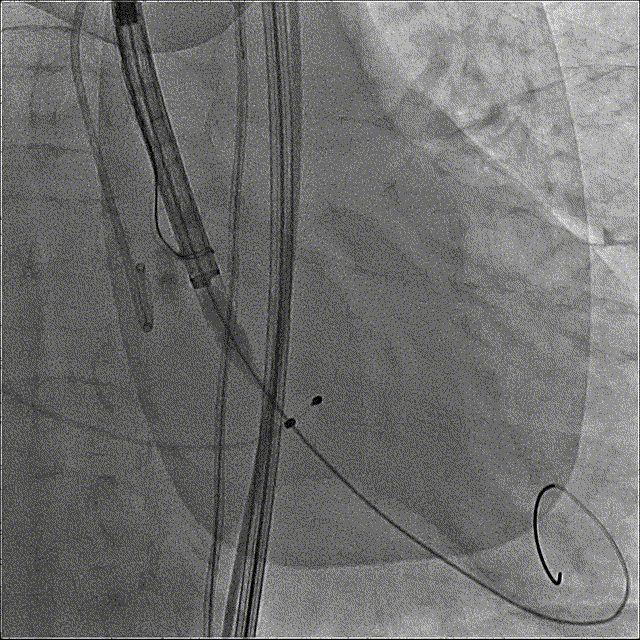

术后即刻压差从81mmHg下降至23.9mmHg

最终造影

主动脉弓剪影,瓣膜植入深度3mm,冠脉显影正常,主动脉弓正常